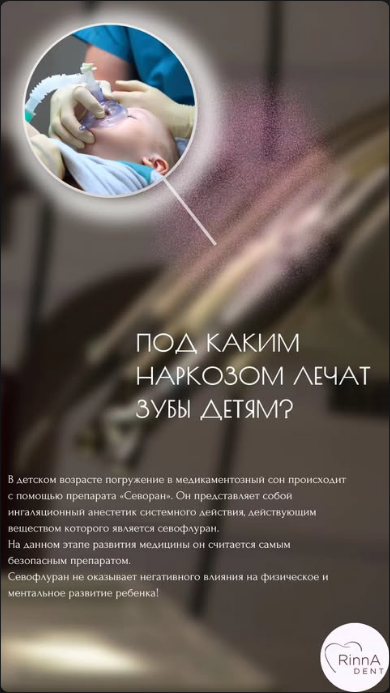

Ключевая услуга клиники

Лечение зубов

Лечение зубов

под наркозом

Используем препарат Севоран (севофлуран) — самый безопасный ингаляционный анестетик на сегодняшний день. Не влияет на физическое и ментальное развитие ребёнка. Всё лечение — за один визит.

💤

Севоран

Безопасный наркоз

✅

Всё за 1 визит

Без повторных стрессов